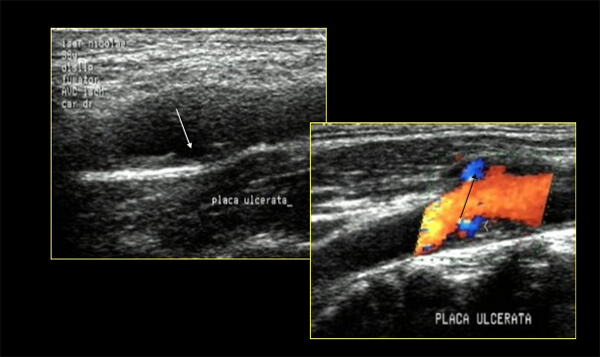

Ο κίνδυνος γιά εγκεφαλικό δεν εξαρτάται μόνο από τον βαθμό της στενώσεως αλλά και από την μορφολογία της αθηρωματικής πλάκας. Μία ασταθής πλάκα είναι επιρρεπής σε ρήξη με σχηματισμό θρόμβου και επακόλουθο εμβολισμό, προκαλώντας ισχαιμικό εγκεφαλικό. Ασθενείς με ασταθή πλάκα χρειάζονται συνήθως περισσότερο επιθετική διαχείριση, ανεξάρτητα από τον βαθμό της στενώσεως.

Διάφορες μέθοδοι χρησιμοποιούνται γιά τον χαρακτηρισμό της μορφολογίας της αθηρωματικής πλάκας:

- Το υπερηχογράφημα είναι πολύ χρήσιμο εργαλείο γιά την εκτίμηση του βαθμού της στενώσεως και της μορφολογίας της καρωτιδικής πλάκας. Σε B-mode brightness ανάλογα με τον βαθμό της ηχογένειας (GSM, gray scale median score) καθορίζεται η ετρογένεια της πλάκας και διακρίνονται 4 τύποι (κριτήρια κατά Gray-Weale et al). Χαμηλό GSM score σχετίζεται με υψηλή περιεκτικότητα σε λιπίδια και αιμορραγία μέσα στο νεκρωτικό πυρήνα της πλάκας, άρα ασταθή πλάκα. Με χρησιμοποίηση σκιαγραφικού (μικρο-φυσσαλίδες) μπορεί να δεί κανείς νεο-αγγείωση της πλάκας. Επαναλαμβάνουμε ότι τα αποτελέσματα της εξετάσεως αυτής εξαρτώνται από τον ιατρό που διενεργεί την εξέταση και ότι μπορεί να δώσει συχνά ψευδώς θετικά αποτελέσματα.